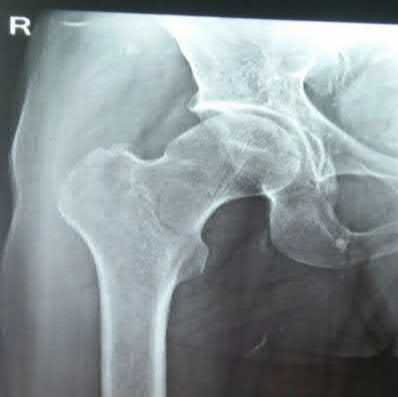

Question 1:

A 12-year-old obese boy presents with vague left thigh and knee pain. He is diagnosed with a Slipped Capital Femoral Epiphysis (SCFE) as seen in similar clinical scenarios. During percutaneous in-situ fixation, unrecognized penetration of the guide wire into the hip joint occurs. What is the most likely specific complication resulting from this technical error?

Correct Answer: Chondrolysis

Explanation:

Chondrolysis is a severe complication of SCFE characterized by rapid destruction of the articular cartilage. While it can occur idiopathically, its most established iatrogenic cause is unrecognized intra-articular hardware penetration. The 'approach-withdraw' fluoroscopic technique is required during pinning to assure pins are entirely intraosseous. Avascular necrosis (AVN) is usually due to damage to the epiphyseal blood supply (retinacular vessels) secondary to the initial displacement, forceful closed reduction, or posterosuperior pin placement.